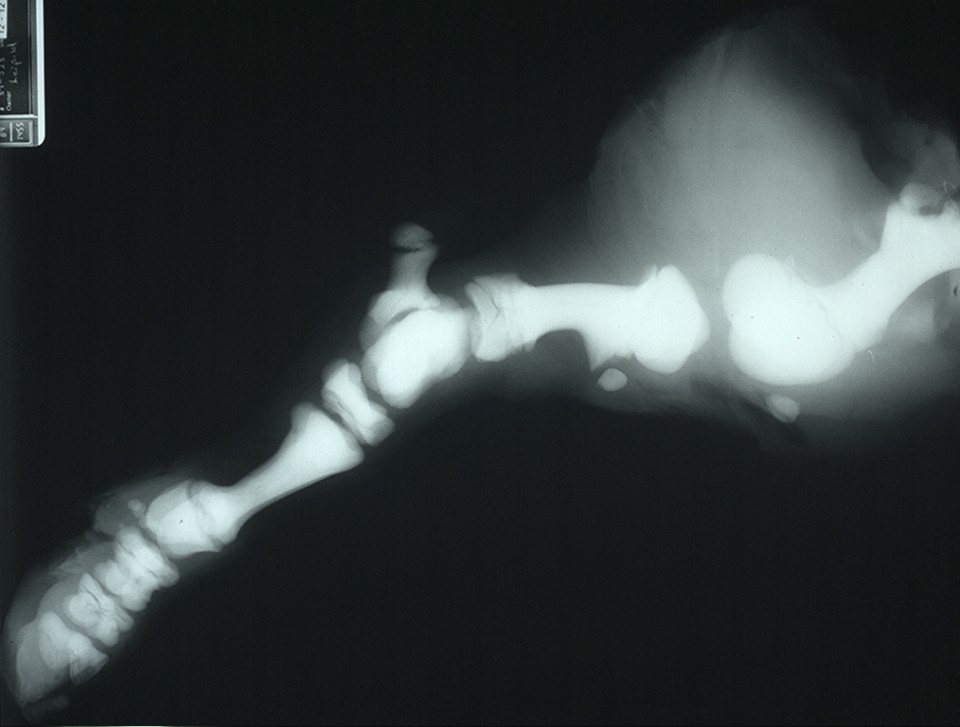

Figure 3 from Osteopetrosis (Marble Bone Disease) A Rare Disease in Children Semantic Scholar Define Marble Bone Disease Osteopetrosis, or marble bone disease, is a rare skeletal disorder due to a defective function of the osteoclasts. Therefore, the disease is often referred to colloquially as “marble bone disease.” the disease was originally described by a radiologist. The disease progresses as long as bone growth. Osteopetrosis is a congenital metabolic bone disease caused by defective osteoclastic resorption of immature. Define Marble Bone Disease.

EXAMS AND ME Skull X Ray and Pathologies Define Marble Bone Disease The disease progresses as long as bone growth. Excessive formation of dense trabecular bone and calcified cartilage, especially in long bones, leading to obliteration of marrow spaces and to anemia. Osteopetrosis, or marble bone disease, is a rare skeletal disorder due to a defective function of the osteoclasts. Marble bone disease, rare disorder in which the bones become extremely dense,. Define Marble Bone Disease.